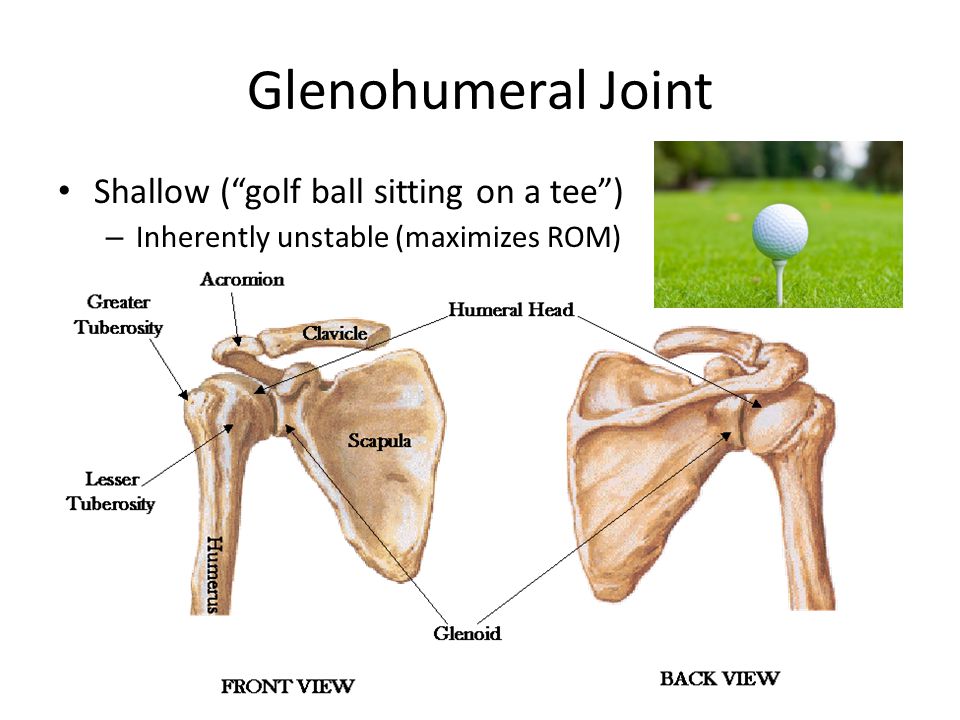

Glenohumeral ligament: анатомия и функции плечевого сустава